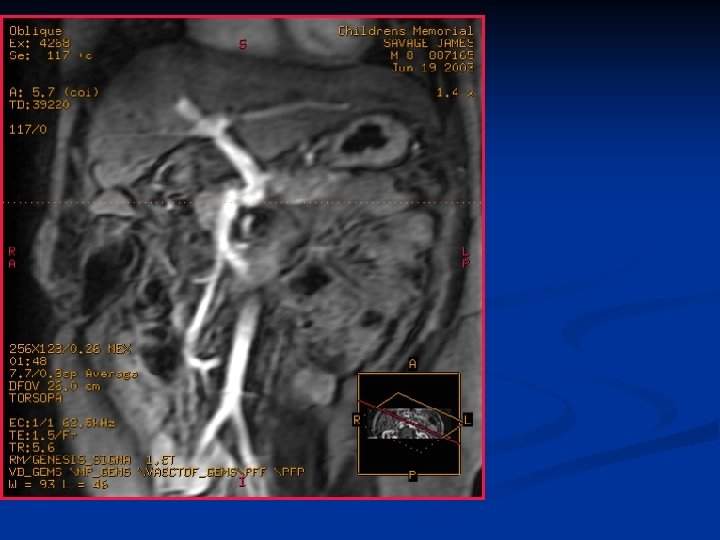

3 -D Tomografia Computadorizada Portografia

CONCEITO DO REX SHUNT MESO-LEFT PORTAL BY PASS 1 - LOCALIZAÇÃO PELO LIGAMENTO REDONDO DO FÍGADO DO RAMO ESQUERDO DA VEIA PORTA- INTRA HEPÁTICA 2 - DETERMINAR PATENCIA DO FLUXO PORTAL INTRAHEPÁTICO 3 - REALIZAR SHUNT MESENTÉRICO –PORTA ESQUERDA – JUGULAR- ILÍACA